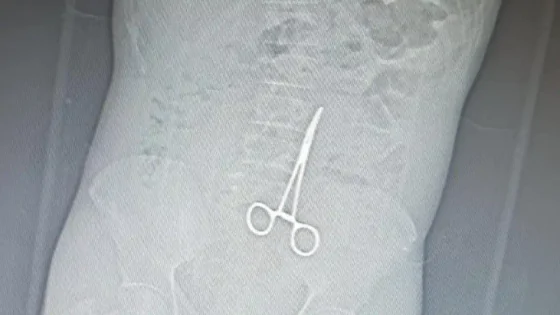

Paciente descobre pinça cirúrgica esquecida em seu abdômen após cirurgia em Parau...

01 de Novembro de 2024